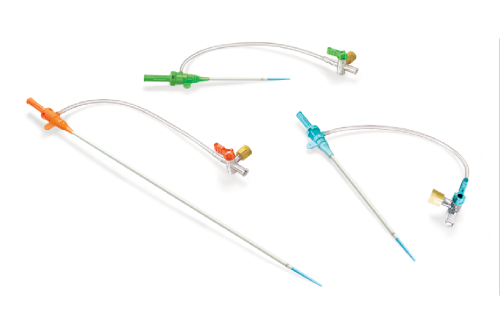

Na área de Cardiologia Intervencionista, fornecemos dispositivos de ponta, como stents, cateteres e balões, que são essenciais para a realização de angioplastias e outros procedimentos cardíacos minimamente invasivos. Nossos produtos são projetados para oferecer máxima eficiência e segurança, contribuindo para a rápida recuperação dos pacientes e a redução de complicações pós-operatórias.

Em Cirurgia Vascular, Endovascular e Radiologia Intervencionista oferecemos uma ampla gama de soluções, incluindo enxertos endovasculares, cateteres de trombectomia e dispositivos de embolização. Esses produtos são vitais para o tratamento de doenças vasculares complexas, como aneurismas e tromboses, proporcionando aos profissionais de saúde as ferramentas necessárias para intervenções precisas e eficazes.

Nossa atuação em Neurorradiologia Intervencionista inclui a oferta de microcateteres e stents especializados para o tratamento de aneurismas cerebrais e outras condições neurológicas críticas. Esses dispositivos são desenvolvidos com tecnologia de ponta para garantir a máxima segurança e eficácia durante os procedimentos, ajudando a preservar a integridade cerebral dos pacientes.